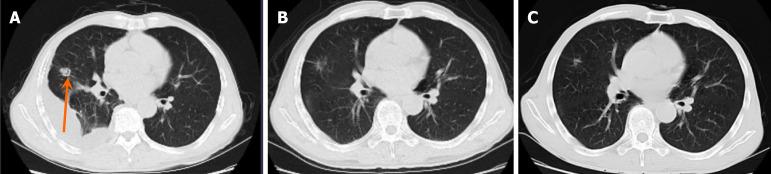

After the fifth cycle of treatment, the patient developed skin itching and a vitiligo-like rash, which are known side effects of immunotherapy. Despite dermatological consultation and treatment with topical corticosteroids, the rash worsened while the itching subsided. The patient continued with the treatment, and after 15 cycles, the tumor showed a response with a reduction in size. The vitiligo-like rash increased, but the antitumor treatment remained effective.

The case highlights the use of immunotherapy in patients with non-small cell lung cancer and the potential side effect of vitiligo-like rash. The patient's tumor responded well to the treatment, and despite the skin reaction, the treatment was not discontinued due to its effectiveness. The article suggests that further studies are needed to understand the mechanism behind vitiligo in patients with lung cancer receiving immune checkpoint inhibitors and whether the development of vitiligo-like rash after immune checkpoint inhibitor therapy is associated with improved prognosis. The case also underscores the importance of managing immune-related adverse events in the context of effective antitumor treatment.